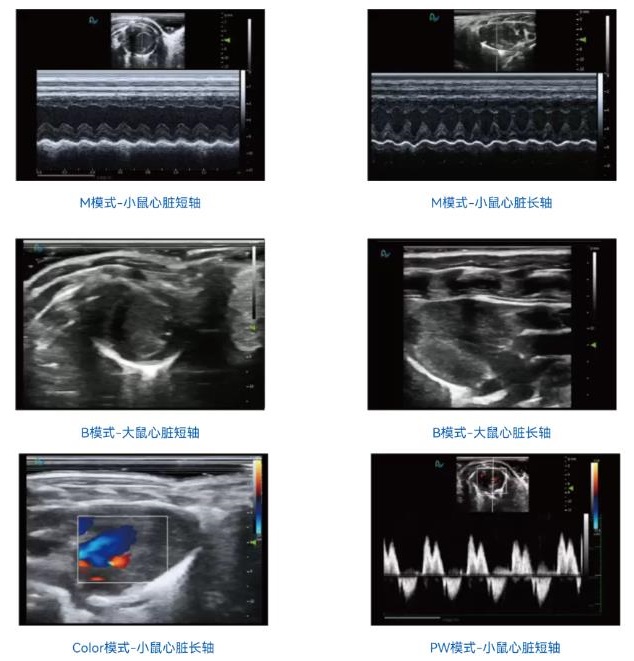

心肌应成像

心脏研究的重要工具:心肌应变成像可无创、实时地评估心肌功能,帮助研究者深入探索心血管疾病的发病机制、药物疗效及基因功能

全面评估心肌功能:应变成像提供多维度应变分析,帮助全面了解心肌在不同方向的收缩和形变,提升诊断的精确度

定量分析:应变成像可以量化心肌的形变,为心脏功能提供精确的数值参数

检测同步性:通过测量不同心肌节段的形变,应变成像可以发现心肌收缩的不同步性

成像效果展示